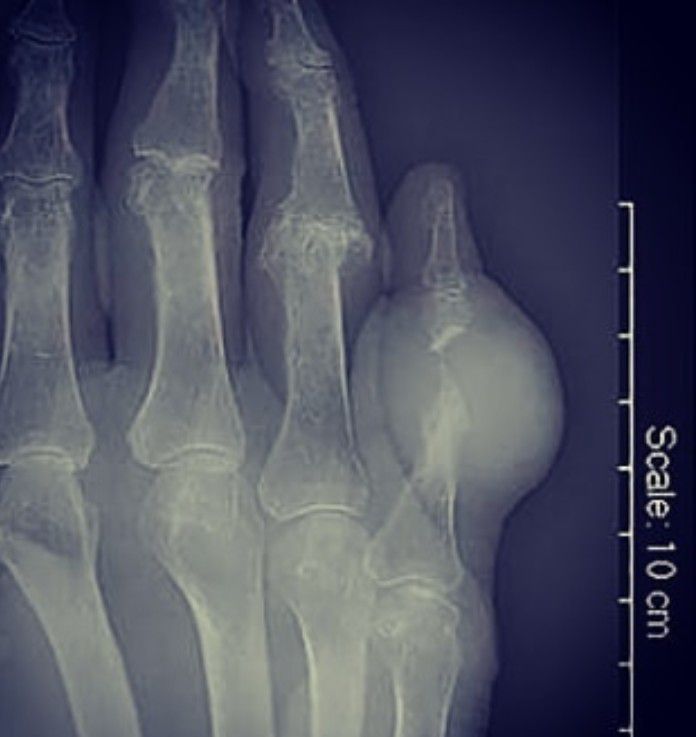

Gout flare-ups occur when uric acid forms crystals that settle in a joint, often the big toe, where it causes warmth, redness, and excruciating pain. One highly visible manifestation is gout tophi, or large bumps that form where gout crystals have accumulated.